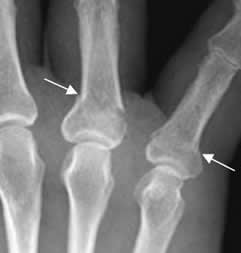

Fig 46. Fractura no desplazada.

Rx AP. Fracturas no desplazadas en las bases del 3º y 4º metacarpianos, cuyos fragmentos permanecen en contacto.